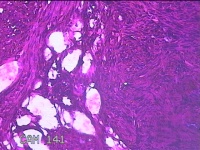

宫腔粘连组织

性别

女

年龄

38岁

临床诊断

1.药流不全 2.宫腔粘连

一般病史

药物流产厚阴道出血10天。

标本名称

大体所见

灰白暗红色不规则碎组织2x1.3x0.8cm一堆。